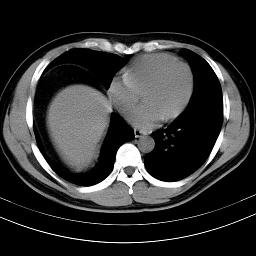

标题: CT18388:肝脏膈肌间隙内大量脂肪密度影 [打印本页]

标题: CT18388:肝脏膈肌间隙内大量脂肪密度影

考虑----气腹可能性大---进一步检查

是脂肪不是气体,有时候会碰到这样的病人,脂肪过多吧。

膈下脂肪沉积。

考虑膈下脂肪沉积。

激素治疗的病人容易脂肪沉积